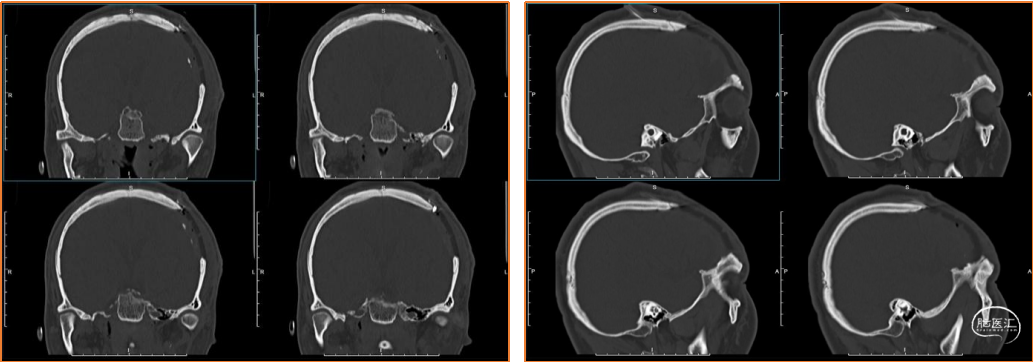

术前检查

术前诊断

1. 脑外伤后遗症,癫痫。

2. 颅骨修补材料凹陷。